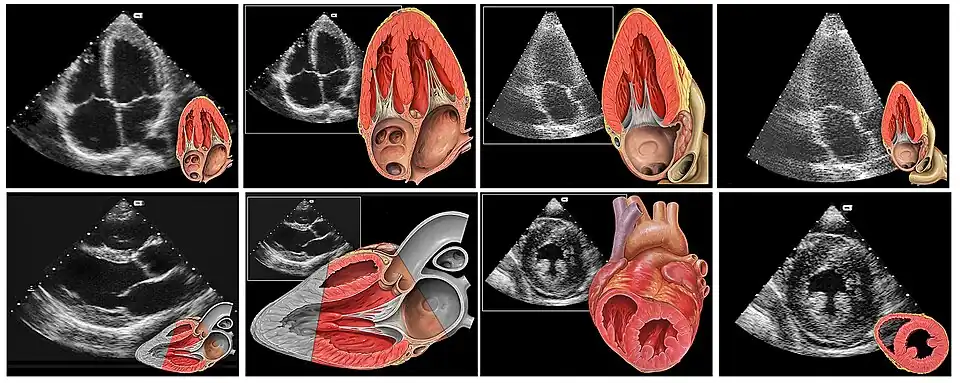

Verschiedene Schnittebenen durch das Herz und korrespondierende echokardiografische Abbildungen.

1. Reihe: apikaler 4-Kammer-Blick, apikaler 3-Kammer-Blick

2. Reihe: parasternale lange Achse (Diastole), parasternal kurze Achse